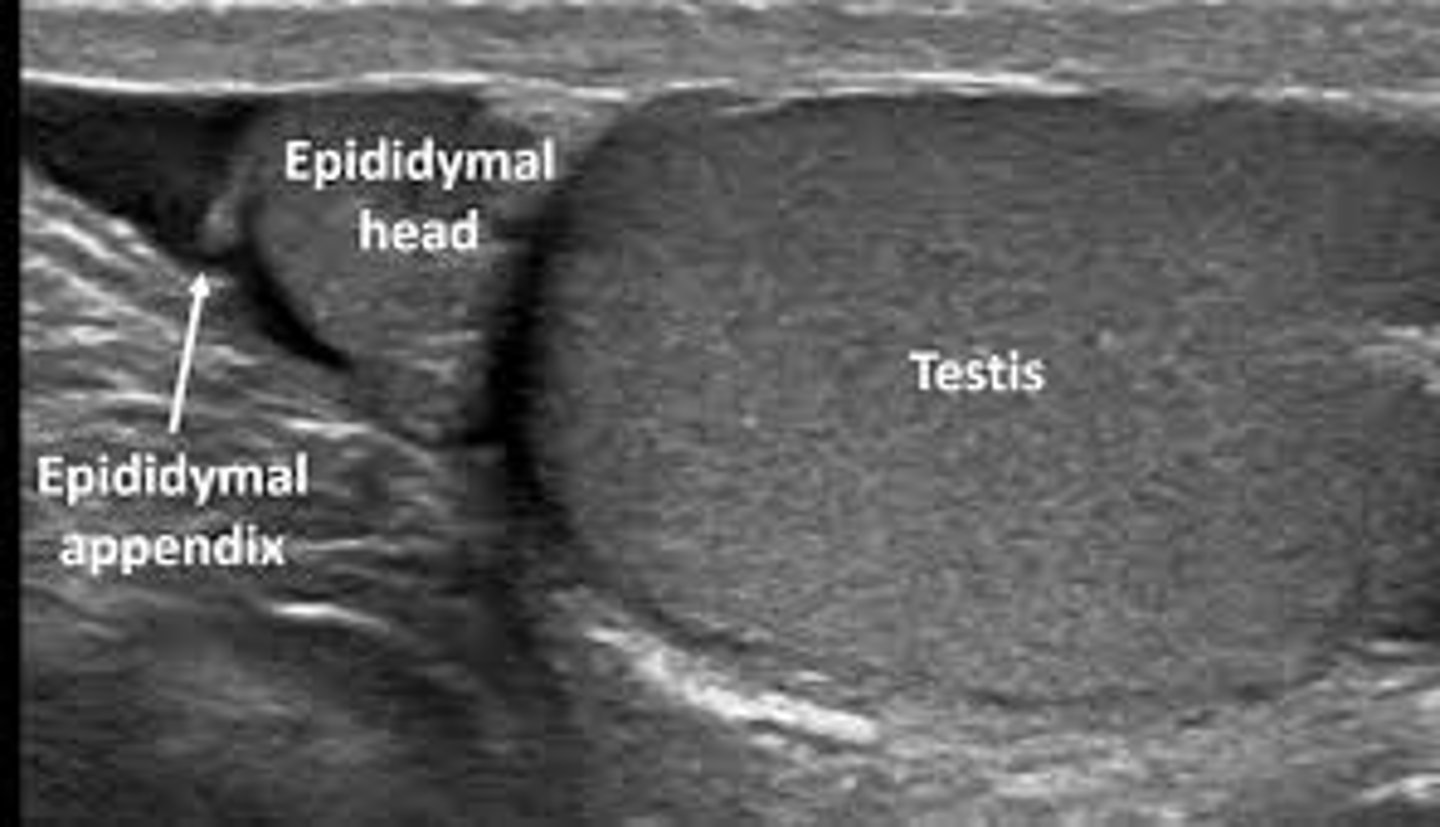

Which of the following structures is located between the head of the epididymis and the superior pole of the testis?

a. Appendix epididymis

b. Appendix vas

c. Appendix testis

d. Tunica albuginea

Which of the following structures is located at the head of the epididymis?

a. Appendix testis

b. Appendix epididymis

c. Appendix vas

d. Mediastinum testis